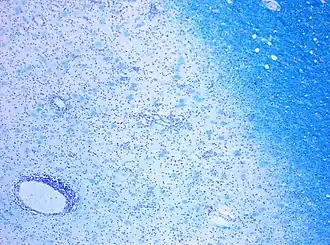

CD68-stained tissue shows several macrophages in the area of a demyelinated lesion caused by MS.

Demyelination in MS: On Klüver-Barrera myelin staining, decoloration in the area of the lesion can be appreciated.